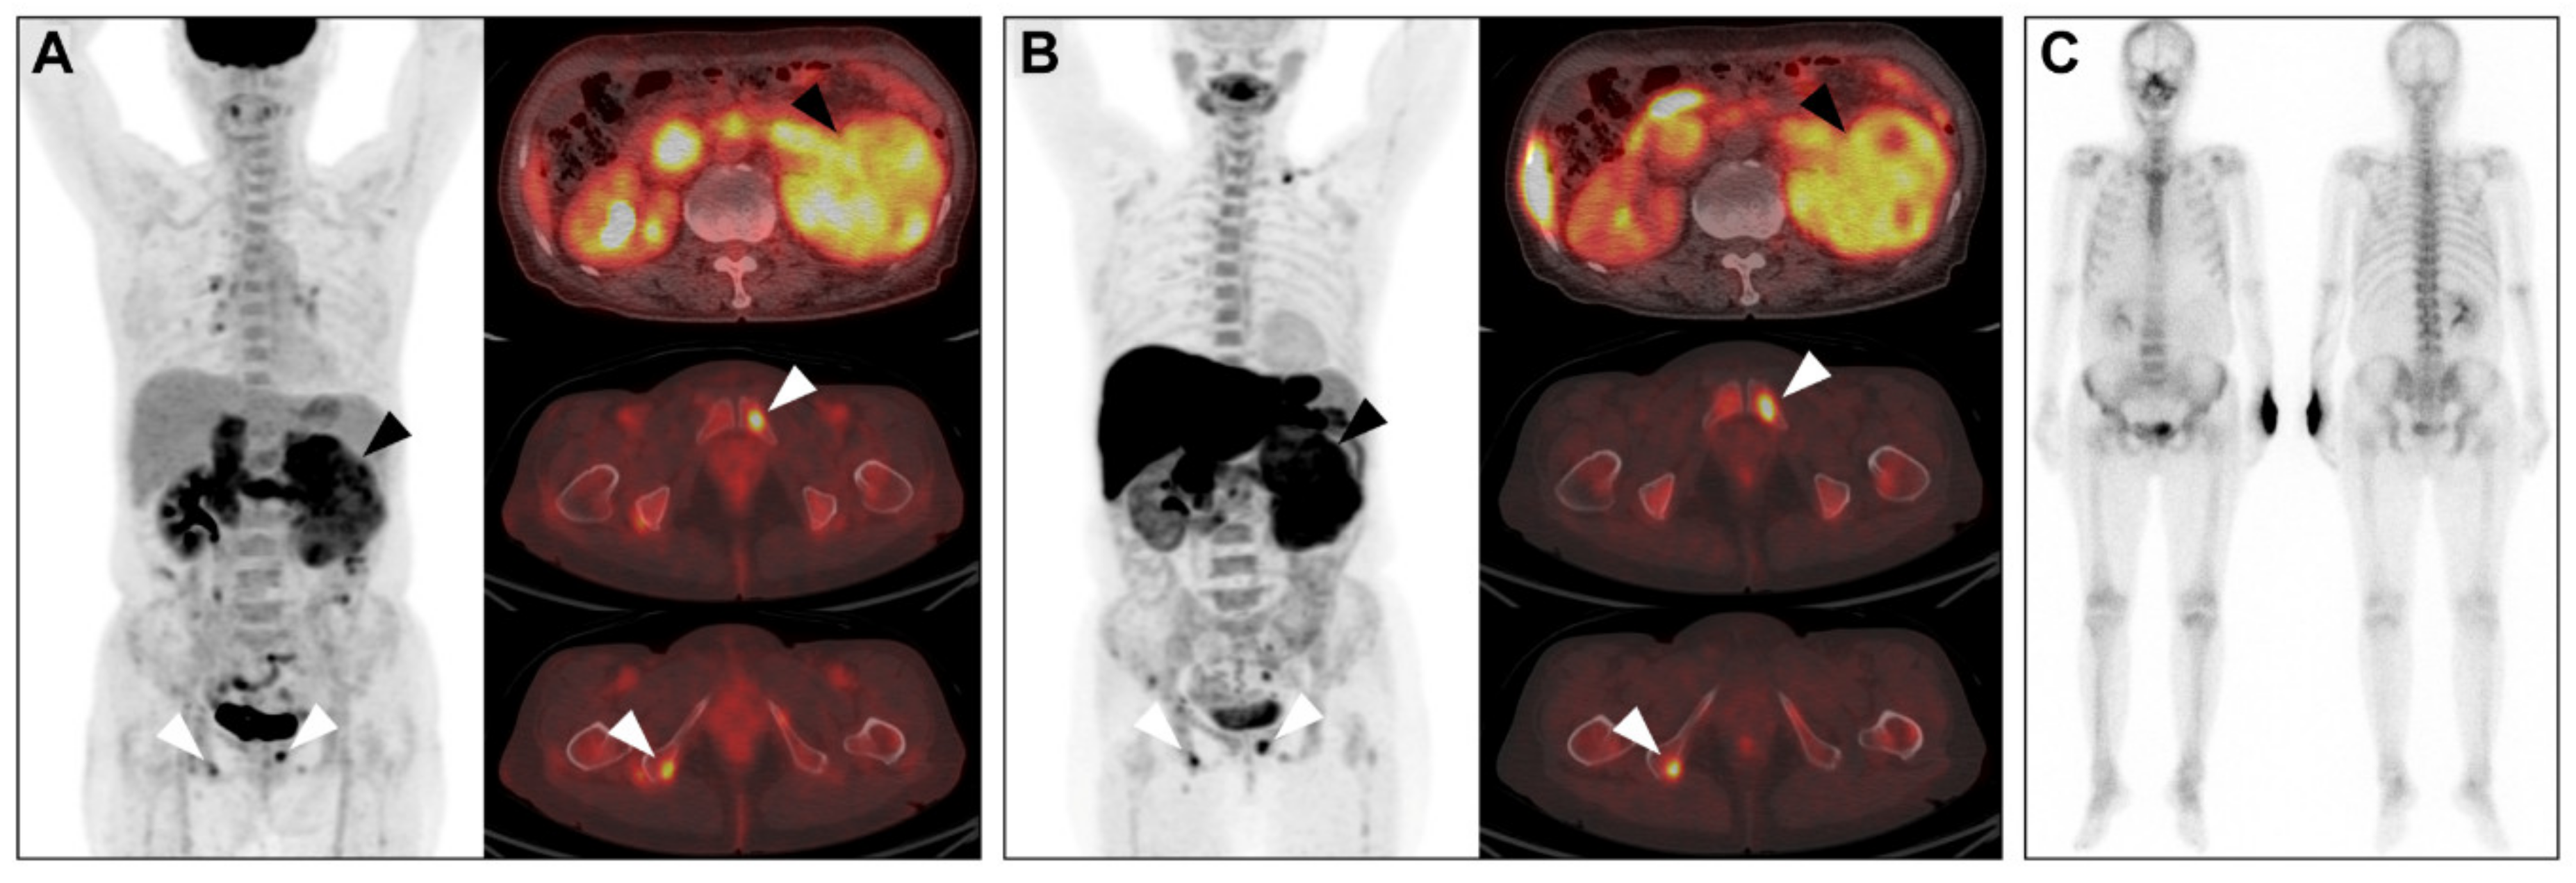

2.4. Comparison of Detection of Extra-Renal Metastases between Conventional Imaging and PET/CT

3. Discussion